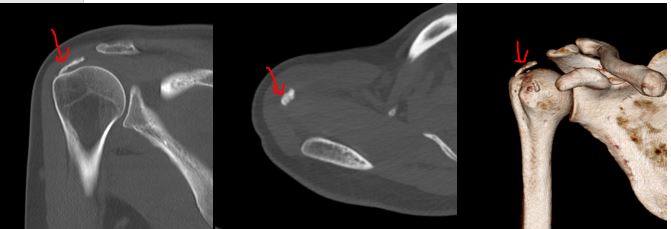

X线提示:肱骨头上方钙化灶

CT上可以看见钙化灶沉积在冈上肌腱周围

通过X线 /CT/MRI可以很容易诊断为肩袖钙化性肌腱炎,并通过关节镜微创手术,得到了根治!

手术后复查X线和CT可以可见钙化灶已经完全清理了。